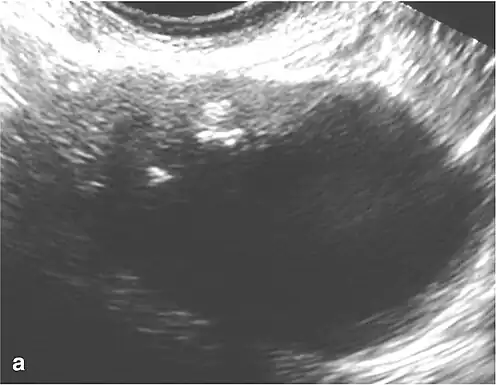

Benign mixed Brenner tumor and mucinous cystadenoma of the right ovary. (a) Transvaginal ultrasound images show mixed cystic and solid components, with calcifications in the solid portion (arrow); (b) Macroscopic evaluation revealed an ovary partially replaced by a solid and cystic tumor[2]

Brenner tumors (BT) are infrequent ovarian growths composed of specialized ovarian cells surrounded by dense fibrous tissue. Typically small (less than 2 cm), these tumors are often discovered incidentally in women without apparent symptoms.[2] However, when a BT is borderline or malignant, indicating a potential for cancer, it may lead to symptoms such as an abdominal lump, abdominal pain, and post-menopausal bleeding. Less common signs include nausea, vomiting, back pain, bowel problems, reduced appetite, and weight loss.

Differentiating between benign (non-cancerous) and malignant (potentially cancerous) BTs poses a challenge as they appear similarly in medical images.[13] The definitive diagnosis involves examining tissue under a microscope (histopathology). Benign BTs exhibit a consistent fibrous structure, a distinctive characteristic. They may also manifest as a cystic mass with multiple compartments, particularly associated with other ovarian growths.[14]